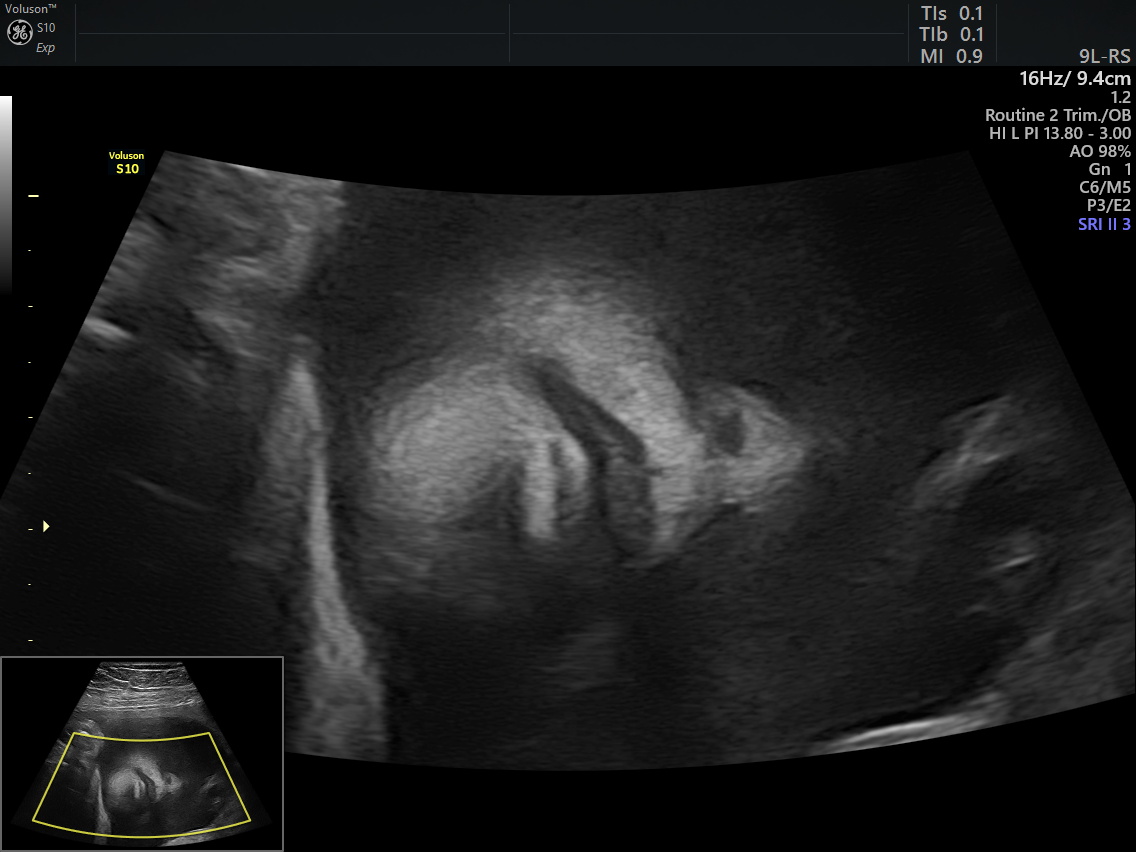

Échographie du 2e trimestre

Cet examen est réalisé entre 20 et 25 SA, idéalement autour de 23-25 SA. Il est réalisé par voie abdominale. Rarement, nous avons besoin de compléter l’examen par voie vaginale pour étudier le col, le placenta ou une structure fœtale bas située.

Il a pour objectif principal d’examiner la morphologie du fœtus et de dépister une éventuelle malformation. Nous contrôlons également sa croissance, sa quantité de liquide et le placenta. En cas de difficultés, un nouvel examen de contrôle pourrait vous être proposé pour compléter l’étude anatomique.